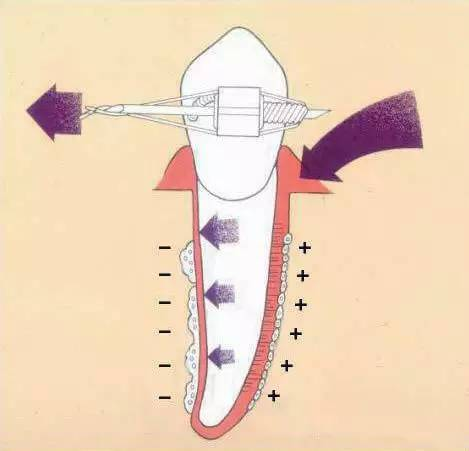

误区11 矫治力越大,牙齿移动越快,矫治力小,不疼,牙齿移动慢或不移动

牙齿移动是骨细胞参与改建的缓慢的生理性移动,不同于宏观世界的物理力学现象,绝非力量越大速度越快。实际上很小的力量即可启动牙齿移动,力量过大反而会移动停止或带来很多副作用。物极必反,矫正不能超越生理限度。矫正期间只要缩短复诊间隔,就诊频繁一些,就能加快进度继而缩短疗程。

牙齿移动是缓慢的生理性移动,平均一个月最多移动1mm。如果因为着急频繁复诊,牙齿和牙周组织失去了休整的时间,就可能带来不可逆的不良后果。牙齿矫正不能拔苗助长,必须尊重生理规律。